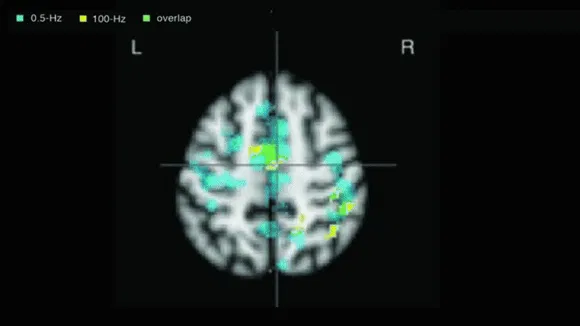

SleepisolのCESテクノロジーのCES(Cranial Electric Stimulation)とは、脳への刺激の一種です。

この脳への電気刺激は、電場や磁場などで使用するのと同じ量のエネルギーを使用することで、頭蓋神経系の機能を変化させます。

この刺激により、脳波の変化やホルモンの分泌量が変化します。

CESは、外耳道、上顎喉頭接合部、乳様突起、こめかみに設置された電極を通過して、脳に向かう微弱な交流電流を送信します。次に、CESは大脳辺縁系、網状体活性化系、視床下部に参加して、脳シナプスのホルモン産生に影響を与えます。

CESの治療後、セロトニン、βエンドルフィン、メラトニンなどの脳内シナプスホルモンの量が増加することが観察されています。これらのホルモンは感情をコントロールする能力や睡眠障害と深く関係しており、特にセロトニンやメラトニンの量が増えると睡眠障害に効果があることが証明されています。

この驚くべき効果はさておき、CESは血中の既存のコルチゾールを減少させ、脳波をポジティブに変化させます。

CESの信頼性は、f-MRIで確認された頭蓋神経の変化によって検証されています。CESの技術は臨床的に証明され、※FDAによって承認されています。